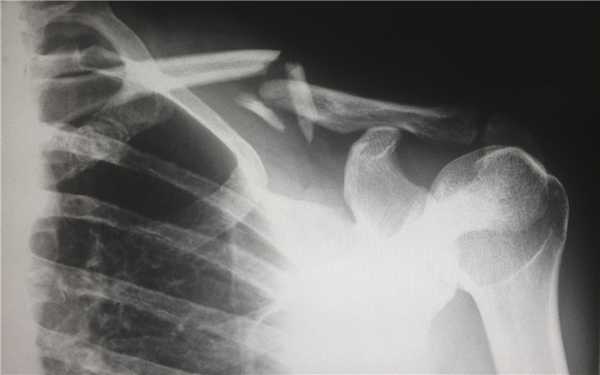

- Рентгенография коленного сустава. Является основным методом инструментальной диагностики. Рентгеновские снимки выполняют в двух проекциях. В абсолютном большинстве случаев это позволят достоверно установить не только факт наличия перелома мыщелков, но и характер смещения отломков.

КТ при переломах

Компьютерная томография (КТ, или МСКТ) является наиболее информативным методом визуальной оценки посттравматических изменений костей, суставов и окружающих тканей. В отличие от других видов лучевой диагностики, при КТ тело человека сканируется поперечно тонкими срезами, на сканах визуализируются ткани различной морфологической структуры (кости, внутренние органы, системы кровообращения и лимфотока), а на основании полученных изображений создается трехмерная модель-реконструкция исследуемой части тела и сканы в трех плоскостях.

Таким образом, будучи пространственным, а не плоскостным (как рентген) методом визуализации любых костных анатомических структур, КТ позволяет достоверно определить тип травмы, увидеть возможные осложнения и повреждения соседних тканей. Поэтому среди врачей это исследование считается предпочтительным для диагностики переломов, особенно осложненных, в том числе внутрисуставных, не рутинных. Плюсом КТ также является оперативность и простота обследования для пациента.

Компьютерная томография позволяет детально визуализировать кости, суставы и окружающие ткани в режиме 3D, что делает этот метод идеальным для диагностики переломов разной степени сложности. Врач-рентгенолог увидит даже небольшое смещение костей, сколы и трещины, а также сможет точно рассчитать любые отклонения с помощью программного обеспечения. На трехмерной реконструкции отсутствуют артефакты (искажения), так что врач сможет точно и достоверно описать результат в заключении.